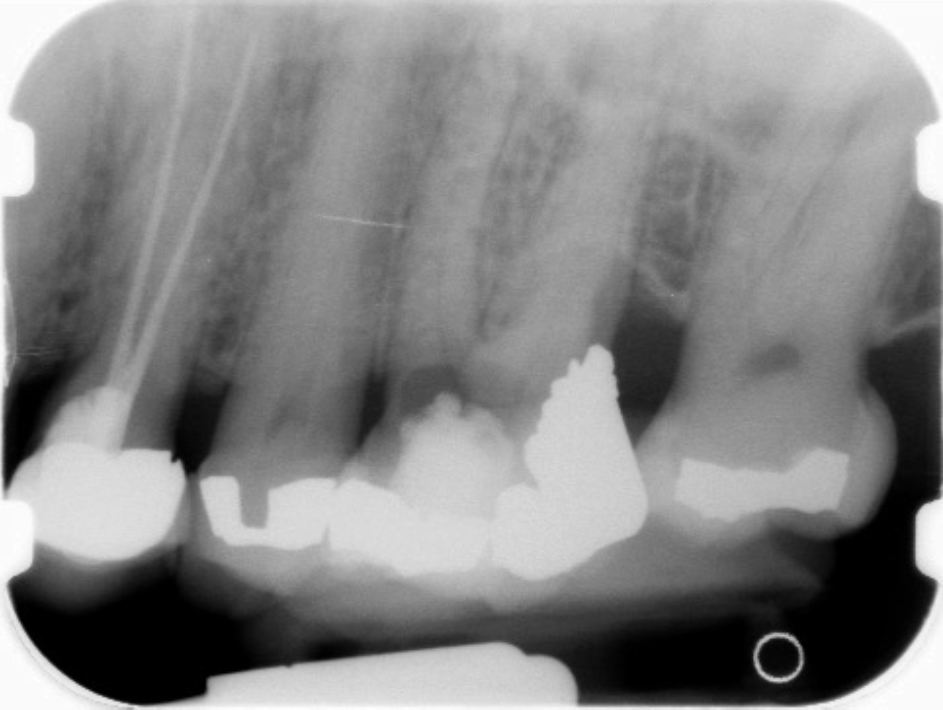

Fig 9 Preoperative radiographs showing mesial perforation.

Figure 9

Fig 10. Preoperative radiographs showing mesial perforation.

Figure 10

Fig 11. MTA perforation repair done, and calcium hydroxide medication placed in the canals.

Figure 11

Fig 12. Postoperative radiograph.

Figure 12

Fig 13. 2-year follow-up radiographs showing the positive outcome.

Figure 13

Fig 14. 2-year follow-up radiographs showing the positive outcome.

Figure 14